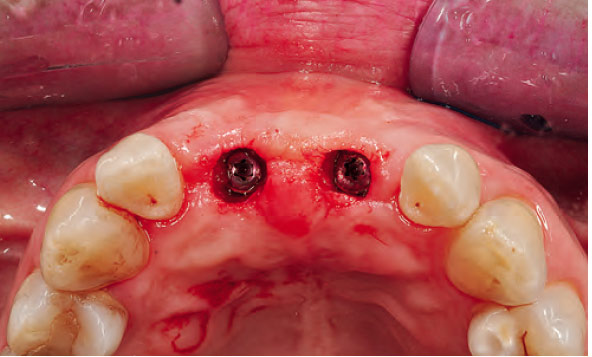

Si, infatti in ciascun capitolo sono presenti numerose immagini cliniche altamente esplicative

allo scopo di enfatizzare l'efficacia didattico-formativa del libro.

Nella gallery sotto alcune foto tratte dai capitoli del libro. Queste foto sono del prof. Eugenio Romeo